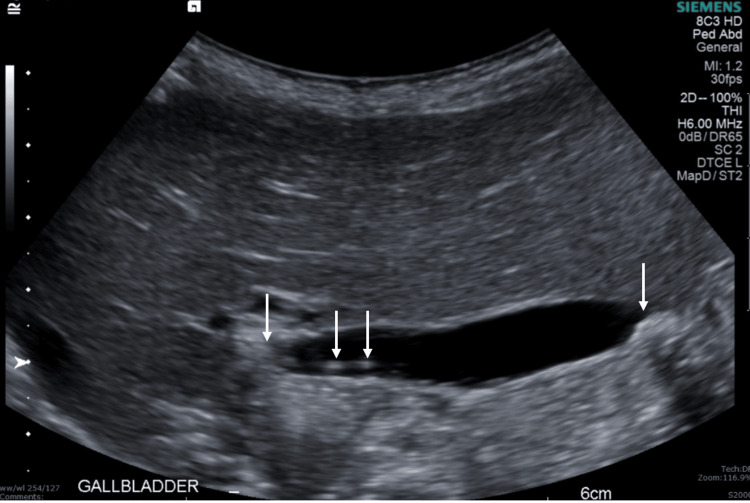

Follow-up US performed two weeks after discharge (Figure 4) showed interval resolution of intra- and extrahepatic biliary duct dilatation and cholelithiasis without evidence of cholecystitis.